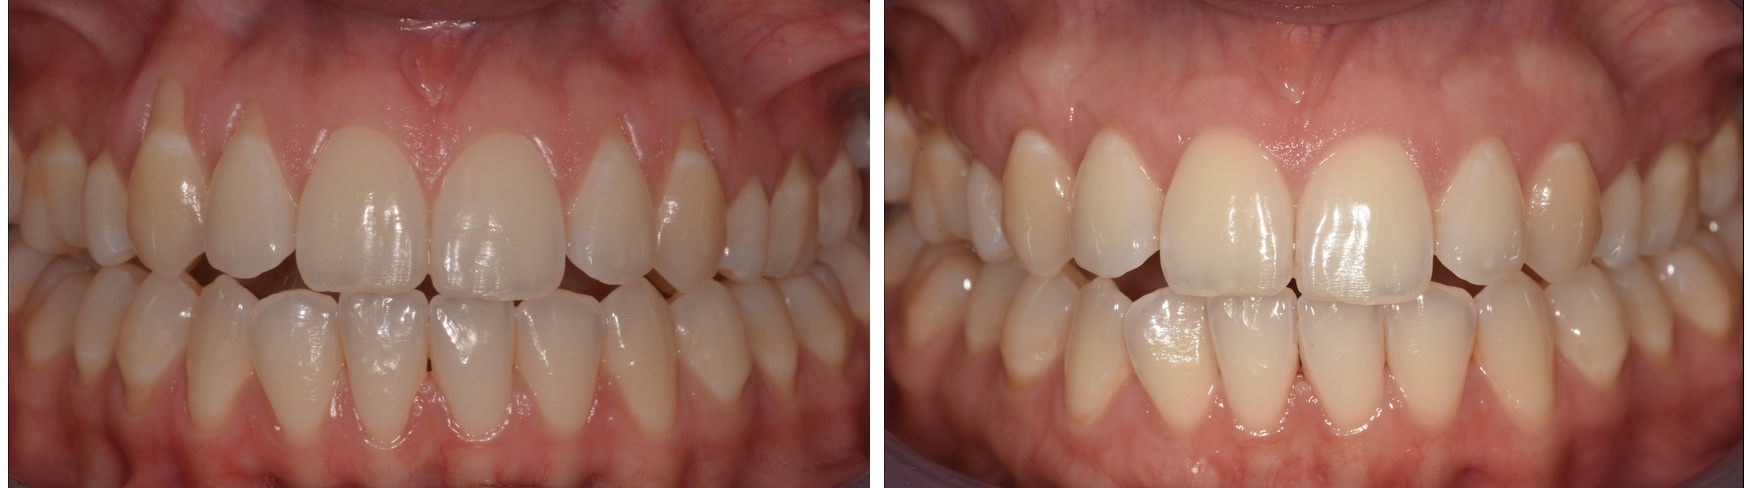

Ínyvisszahúzódás klinikai képe

Sebészeti beavatkozás eredménye